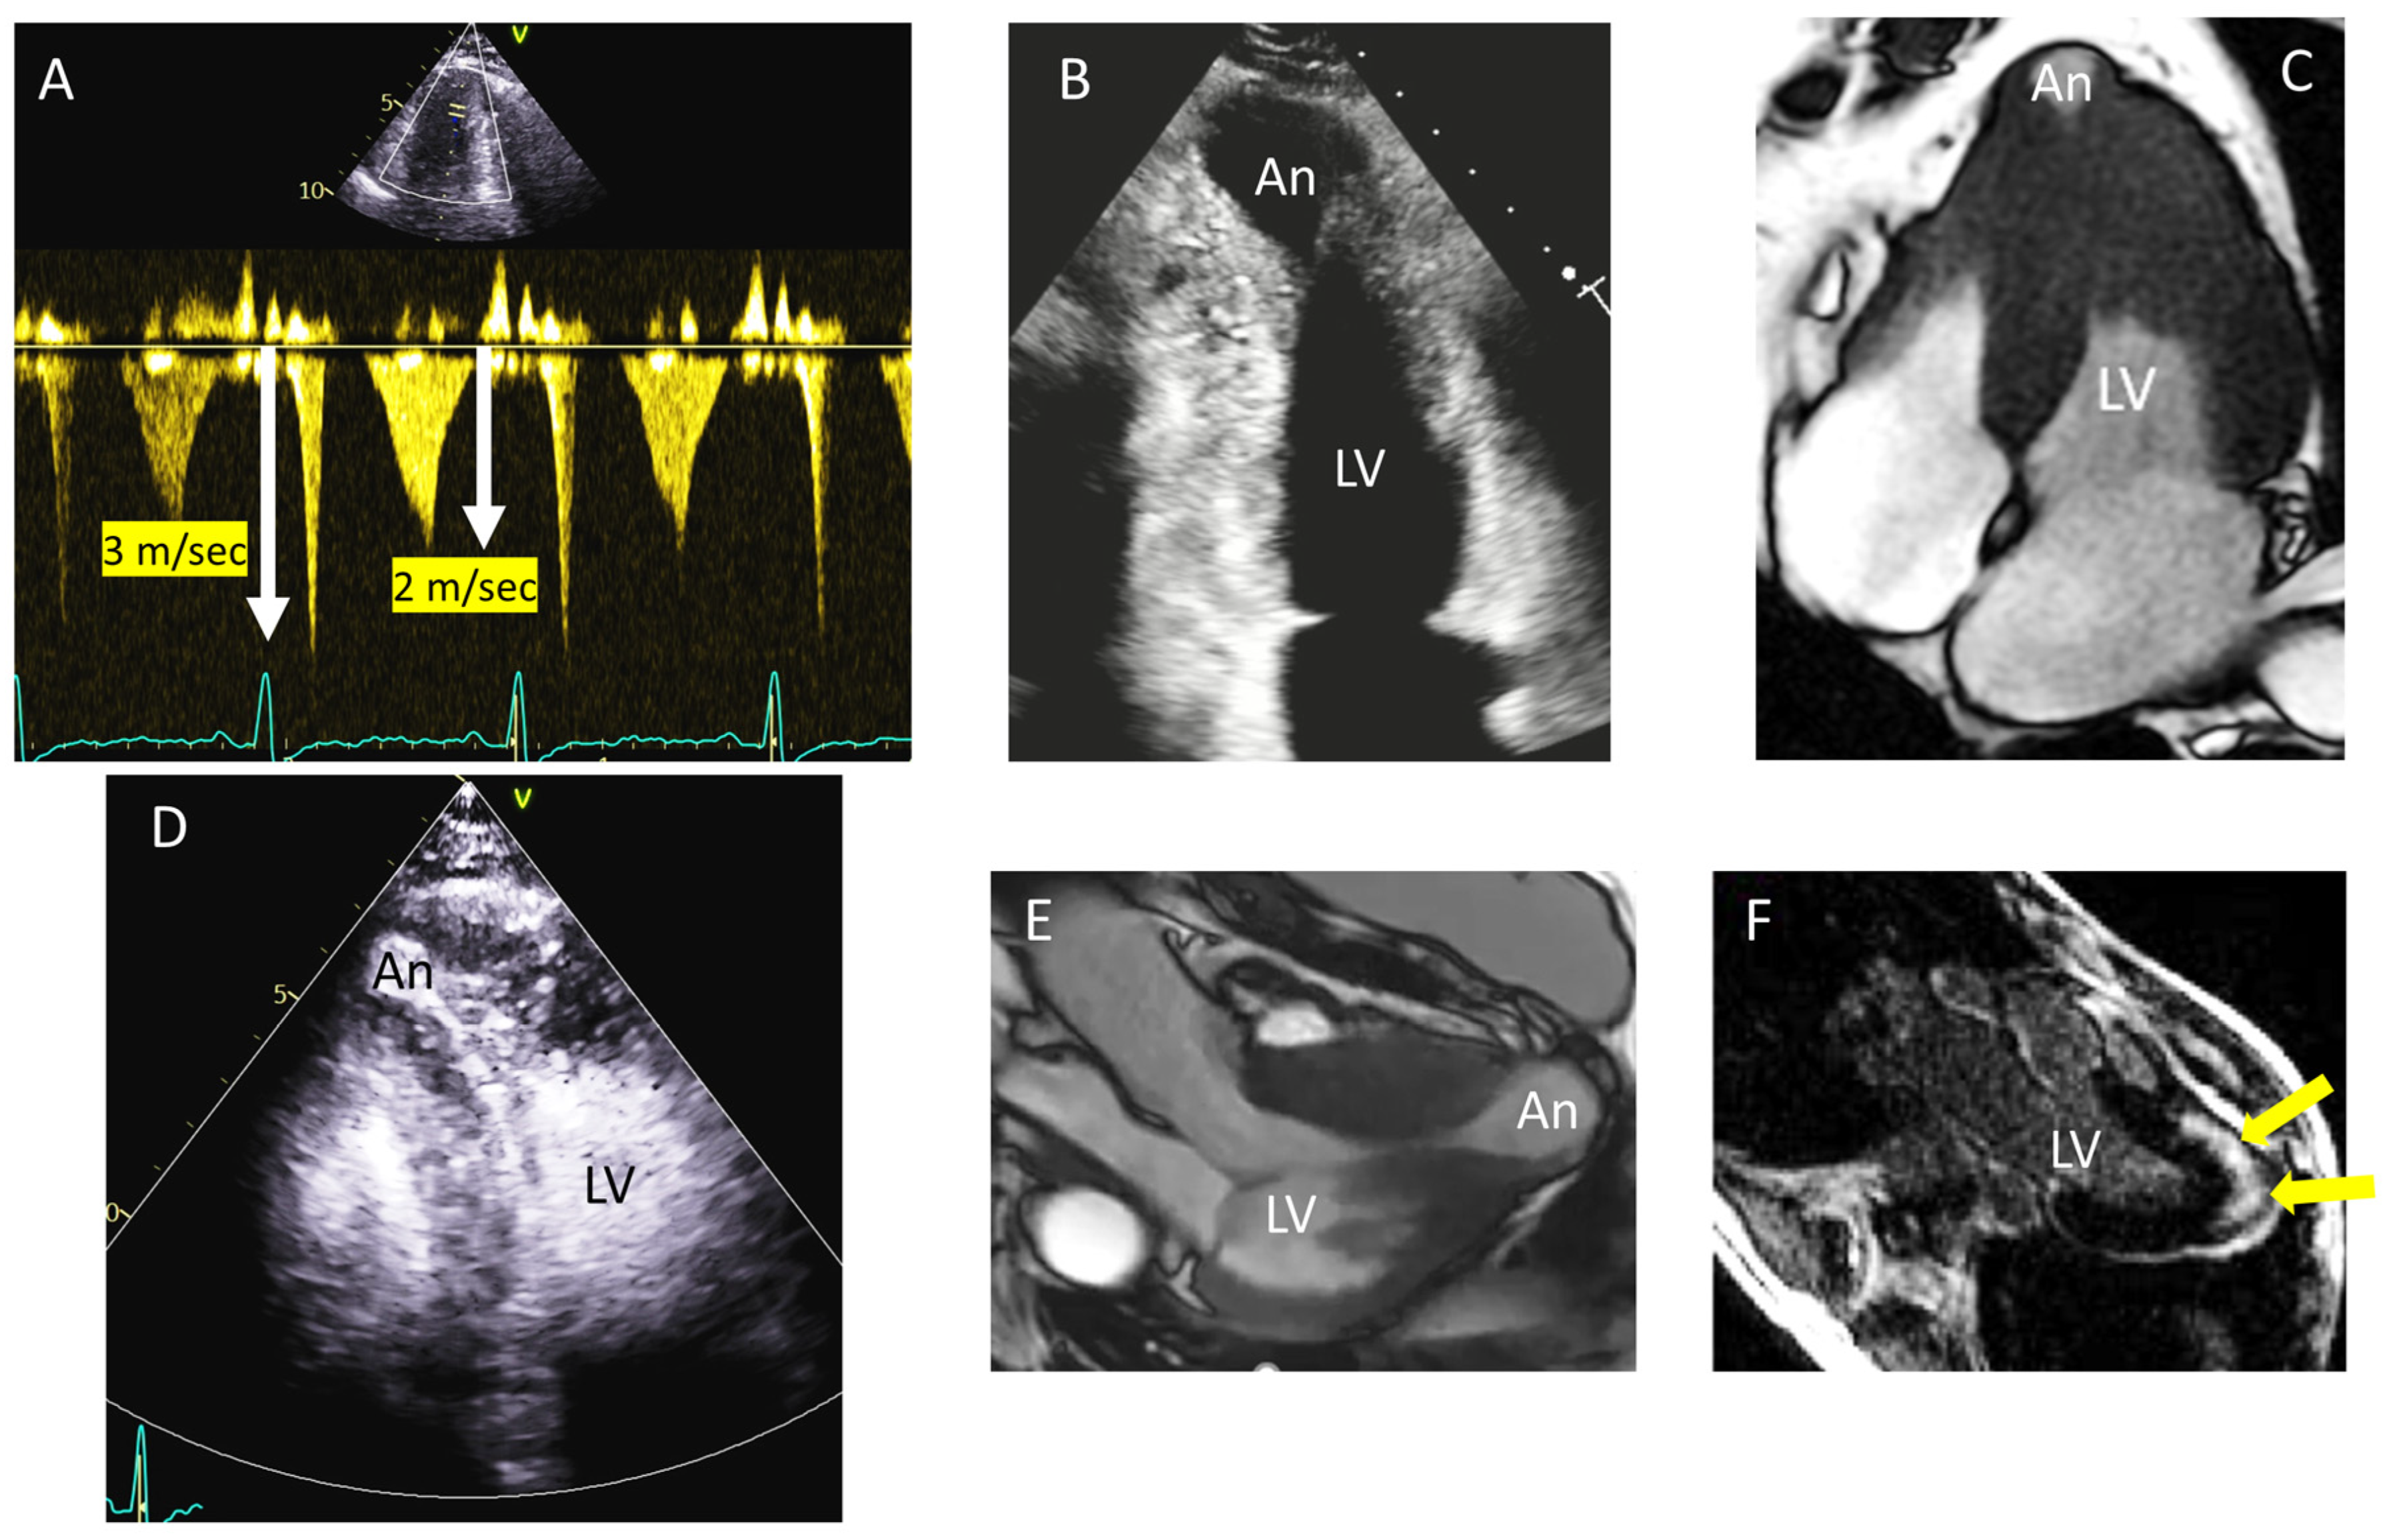

4. Tip and Tricks Concerning LVOT Obstruction Doppler Measurement

- Lo Russo, G.V.; Pepi, M.; Mushtaq, S.; Mantegazza, V.; Celeste, F. Is There a Typical Doppler Pattern in Patients With Apical Hypertrophic Cardiomyopathy With Aneurysm? JACC Case Rep. 2023, 14, 101836. [Google Scholar] [CrossRef]

- Abbasi, M.; Ong, K.C.; Newman, D.B.; Dearani, J.A.; Schaff, H.V.; Geske, J.B. Obstruction in Hypertrophic Cardiomyopathy: Many Faces. J. Am. Soc. Echocardiogr. 2024, 37, 613–625. [Google Scholar] [CrossRef]